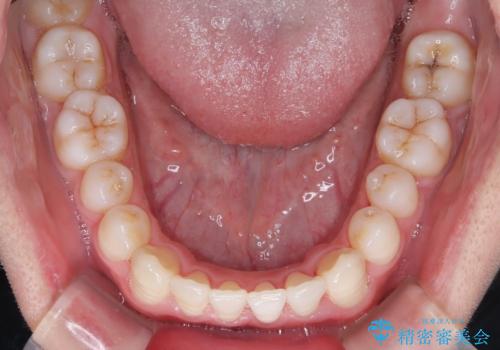

- 前歯のすきっ歯が気になると来院された患者様です。

前歯の隙間をマウスピース矯正(インビザライン)を使用して、閉じていきました。

- 1年2ヶ月